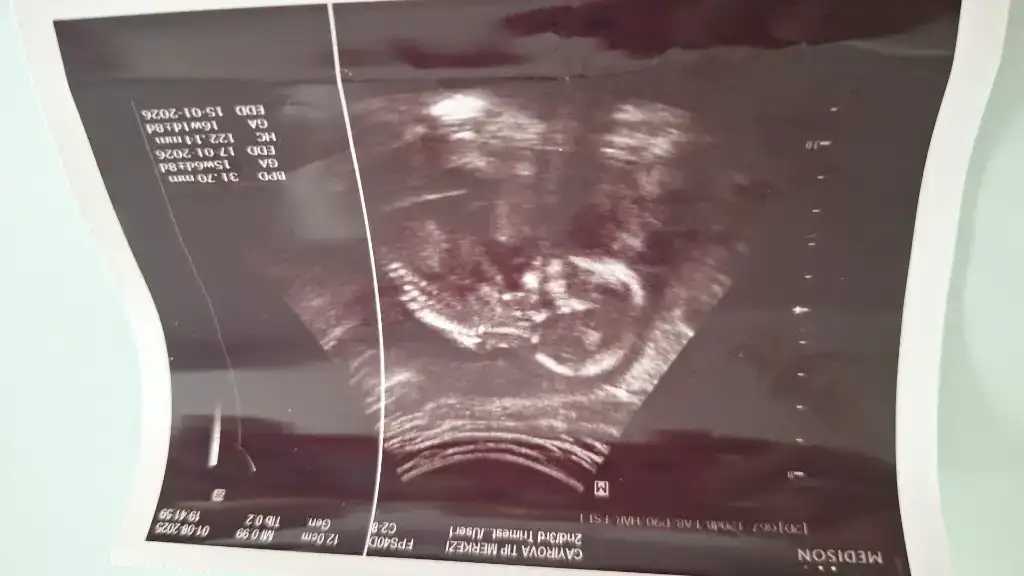

Doktorumun yuzde90 dedigi ihtimali soyledi evetÜcretsiz olan yermi doğru mu bildi yani

Devletteki doktor mu? Cihazlari eski oldugu icin yanilabiliyorlarBende anlamadım geçen haftaki yorumuyla bu haftaki yorumu çok çelişkili neden böyle olduki yanet görmüştük bacak arasını iki çizgiyi, bugünde gösterdi boş ama neden erkekte olabilir dedi buhaftadan önce erkek olduğunu öğrenip pipi görenler var

Benimde 16 hafta 2 gün göstermiyorSelam kızlar bugün kontrolüm vardı aynı zamanda ikili tarama testi için gittim 12+5 haftalık çıktı ultrasonda doktor cinsiyeti göremedim dedibaya da uğraştı sonra radyoloji uzmanı ense ölçerken ona sordum erkeğe benziyor dedi sizin varmı yorumunuz ultrason cihazı kötü biraz

Hayır özel bir hastaneye gitmiştim yani geçen haftayla aynı bunu verdi, ekranda bacak arasını gösterdi boştu kendinde söylüyor boş diye ama çıkıntı var erkekte olabilir kızda diyorDevletteki doktor mu? Cihazlari eski oldugu icin yanilabiliyorlar

Kiz genelde 3 cizgi oluyor ama artik 15 haftada netlesir yani cinsiyet